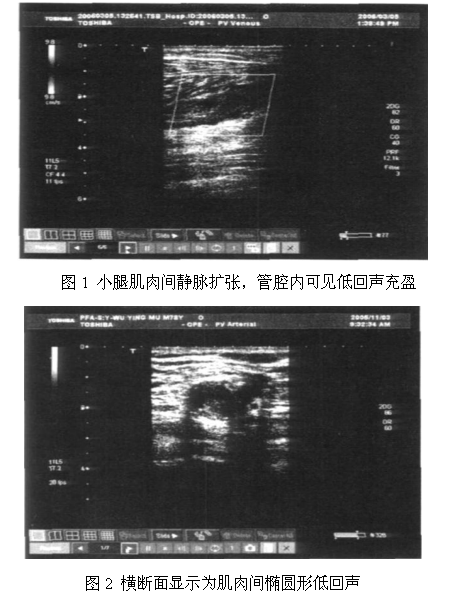

小腿肌间静脉血栓的主要超声表现为管腔明显扩张,走形迂曲,管腔内可见无回声或低回声带,横断面肌肉间呈多个圆形或卵圆形的低回声,长轴切面主要呈树枝状的低回声带,当把探头加压后不能压闭或部分压闭,陈旧性的血栓一般表现为中等回声,管腔可见明显的增厚,当管腔被压瘪后,血流内的信号明显变弱,具体见图1,图2。

本研究结果显示多普勒超声可以对血管管腔形态、血流走向、血液状态进行动态观察,具体表现为小腿肌间静脉血栓的主要超声表现为管腔明显扩张,走形迂曲,管腔内可见无回声或低回声带,横断面肌肉间呈多个圆形或卵圆形的低回声,长轴切面主要呈树枝状的低回声带,当把探头加压后不能压闭或部分压闭,陈旧性的血栓一般表现为中等回声,管腔可见明显的增厚,当管腔被压瘪后,血流内的信号明显变弱,上述患者在1周-1月的抗凝治疗后再对上述患者行多普勒超声检查,发现50例血栓患者中有38例血栓范围明显缩小,回声下发现回声强度减弱或消失,血流流动明显,可探明部分血流信号,18名陈旧性血栓患者的静脉丛中可见部分血流信号。该诊断方式可以对静脉血栓进行双侧对比检查,可见该种诊断方式在静脉血栓的诊断上具有一定的优势,但是在临床实际操作过程中要注意一些细节问题,要充分认识各类血管的特征,以免忽略扫视而延误病情,同时在操作过程中探头加压要轻,以免用力挤压造成栓塞的转移[5],最终形成肺栓塞,小腿部位的静脉较多且较为复杂,所以在诊断的过程中要分别按照各个方向进行多方位、多角度探测[6];同时诊断过程中还要注意与其他疾病的鉴别诊断,常见的鉴别诊断疾病主要包括小腿腓肠肌血肿、肌间静脉丛曲张,由于上述几种疾病发生的病史、症状极为相似,临床上容易造成误诊,所以临床上该病的正确诊断和合理治疗对于疾病的治疗是极为重要的。